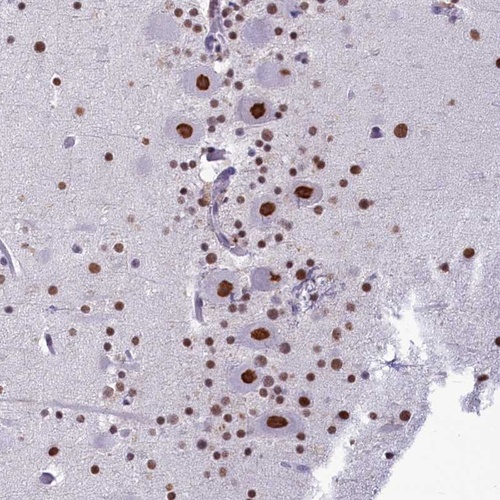

Immunohistochemical staining of human cerebellum shows strong nuclear positivity in Purkinje cells.